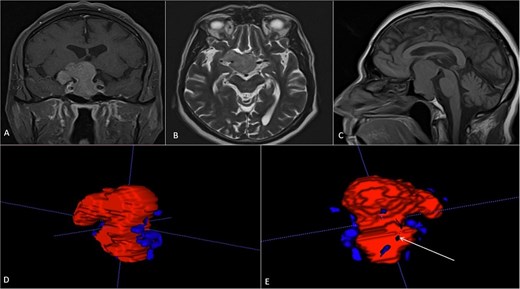

A 71-year-old woman who gradually began with bitemporal hemianopia, progressing to amaurosis of the right eye, adding diabetes insipidus. An MRI study obtained the following images (Fig. 1). 3D reconstruction was performed by manual segmentation to obtain the anatomy of the tumor and its vascular relationships. For this segmentation, it was necessary to splice T2, T1, Contrast, and 3D TOF sequences (Fig. 2). The importance of the reconstruction lies in being able to adequately observe most of the cerebral blood circle and its relationships with the tumor. At the time of carrying out the transnasal resection surgery and keeping in mind the proximity of the anterior communicating artery with the dorso-ventral region of the tumor, the capsule was resected with excessive caution to avoid generating excessive traction and thus avoiding injuries—important vascular (Fig. 3).

MRI of sellar region tumor in contrasted T2 and T1 sequences in axial, coronal and sagittal sections.

3D reconstruction through manual planimetric segmentation of the tumor and its vascular relationships. White arrow, left internal carotid artery. Yellow arrow, anterior cerebral artery segment A2. Red arrow, anterior communicating artery.